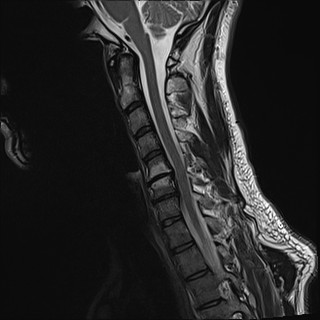

Wirbelsäule HWS

t2_tse_sag